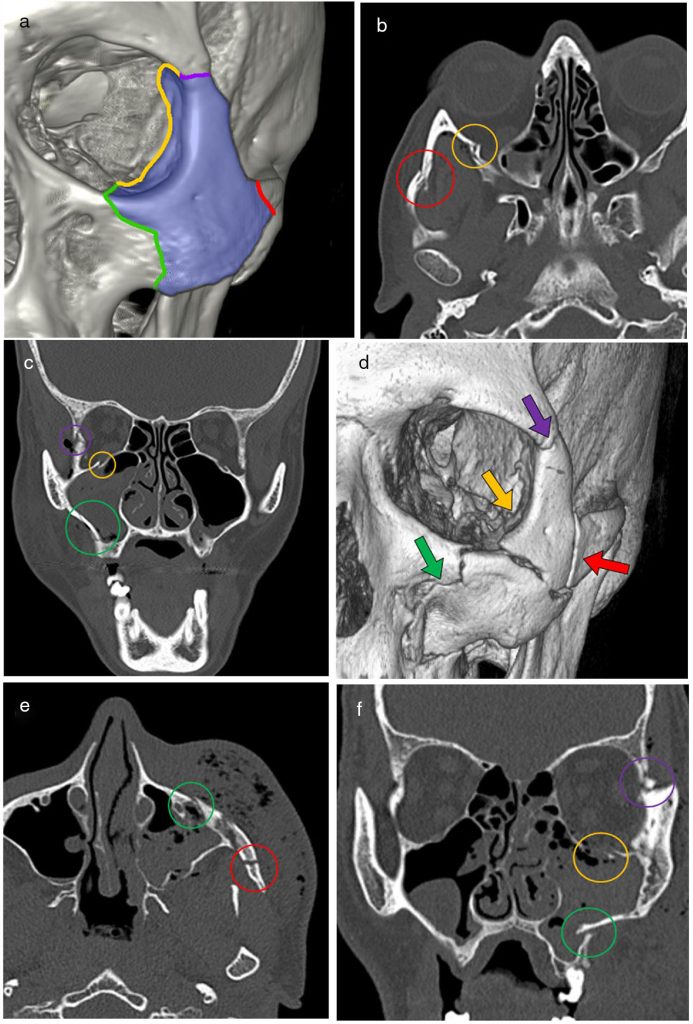

El CBCT (Tomografía Computarizada de Haz Cónico) es la herramienta más precisa para estudiar lesiones faciales. Gracias a su imagen tridimensional, permite detectar fracturas, desplazamientos óseos o daños en raíces dentales que pueden pasar desapercibidos en una radiografía convencional.

- Reconstrucciones 3D que facilitan la planificación quirúrgica.